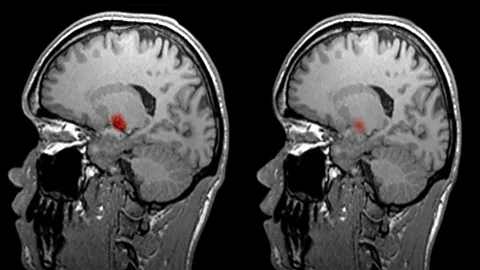

Today, the latest technology to scan the brain is called functional magnetic resonance imaging, or fMRI. I met neuroscientist Joe Devlin from University College London, where he scanned my brain to show me how it was done.

What neuroscientists like Devlin can actually see is my brain’s oxygen change in action. If a certain part of my brain is involved in a certain task, say a language or word task, that area will have an increase in blood flow as it uses energy. The fMRI scanner monitors this blood flow.

SPL“We can see the parts of the brain that lights up as you’re doing that task,” says Devlin.

For example, when I have to actively think about what to say, versus simply counting – a monotonous task that requires little thought – different areas of my brain are active.

While this gives insights into the areas of my brain that are involved in the task of interest, that is not to say fMRI is even close to reading my mind.

That said, scans like this have revolutionised our understanding of the brain. "Traditionally all we had were patients who had brain damage, we could see where they had brain damage and what was wrong with these patient," says Devlin.

But brain scans allow researchers to peer inside the healthy brain to note how different parts are used and how they relate to each other.